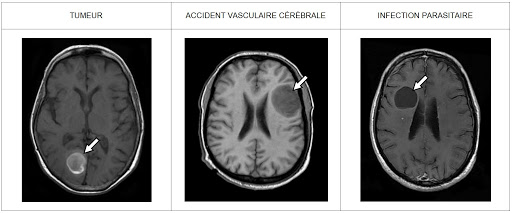

Le parasite en question est Toxoplasma gondii, que vous connaissez peut-être déjà de nom. Jusqu'à récemment, nous ignorions pourquoi tant de personnes étaient concernées par ce parasite, sans pour autant développer de symptômes. Une réponse a été apportée, et nous devons cette découverte à la faculté de médecine de l'Université de Virginie. Grâce à leurs recherches, l'équipe de scientifique pourrait, à l'avenir, comprendre un peu mieux les infections cérébrales, les maladies neurodégénératives, ainsi que les maladies auto-immunes.

Comprendre le rôle des microglies est absolument essentiel puisqu'il s'agit des cellules immunitaires présentes à l'intérieur du cerveau. La découverte effectuée par l'équipe de chercheurs de Virginie met le doigt sur la façon dont les microglies demandent de l'aide en cas de besoin, et cette découverte pourrait bien, à terme, permettre de trouver des solutions pour lutter plus efficacement contre les lésions cérébrales, les maladies neurodégénératives, les AVC, ou encore la sclérose en plaques.

La découverte effectuée par l'équipe de chercheurs est particulièrement importante, puisque pendant des décennies, nous pensions que le cerveau était en quelque sorte déconnecté du système immunitaire. Nous savons à présent que cela est faux. De nombreux scientifiques sont donc, en ce moment-même, en train d'explorer les implications de cette découverte majeure.